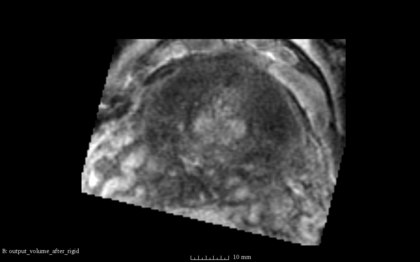

- the following images are shown from left to right:

- [1] Fixed Volume as Reference [2] SimpleITK result after Initialization [3] SimpleITK result after rigid registration [4] BRAINSFit result after rigid without using masks and --useCenterOfGeometryAlign

- The rigid registration result does not reasonable and is a little different with every computation. Reason might be that seed is set randomized and not set as done in BRAINSFit here. There is no option at the SimpleITK::ImageRegistrationMethod to set a metric seed.